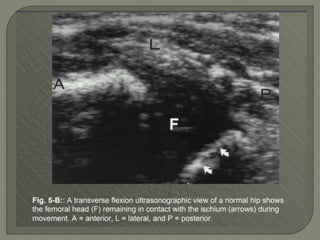

Ultrasound

1]More reliable in revealing a joint effusion in early cases.

Widening of space between capsule and bone of > 2mm

indicates effusion.

2]Echo-free - transient synovitis

3]Positively echogenic septic arthritis

Oblique sagittal ultrasound of the hip of a

17-month-old child with septic arthritis

shows an echogenic effusion and synovitis

S. Arttrities